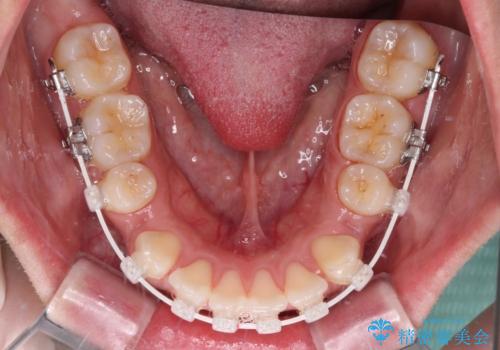

- 矯正装置

- 審美装置

- 前歯の出っ歯と口元の閉じにくさを気にして来院された患者様です。

口元を積極的に引っ込めるために、上下左右の小臼歯4本を抜歯することとしました。

4本の歯を抜歯したことで、飛び出していた口元が引っ込み、横顔の印象が大きく改善されました。